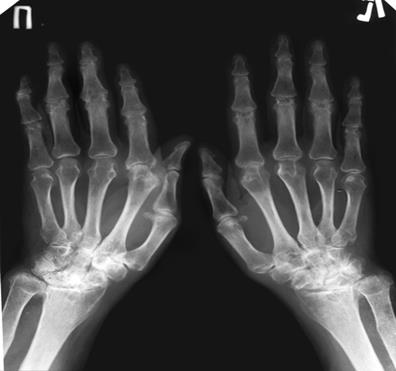

Объективно: состояние средней тяжести, температура тела 38,3°С. Пальпируются периферические лимфоузлы, размером с фасоль. Значительная деформация суставов кисти по типу "шеи лебедя", "пуговичной петли", ульнарная девиация кистей. Гиперемия кожи над мелкими суставами кисти, лучезапястными, голеностопными суставами. Объем движений в пораженных суставах ограничен. Мышцы предплечья, кисти, голени атрофированы. На разгибательной поверхности предплечья в области локтевых суставов пальпируются плотные подвижные безболезненные узелки размером 1,5 см. Границы сердца в пределах нормы, тоны ясные, пульс ритмичный, 80 в мин.

Рис.1. Рентгенография кустей рук больной Е., 34 г.